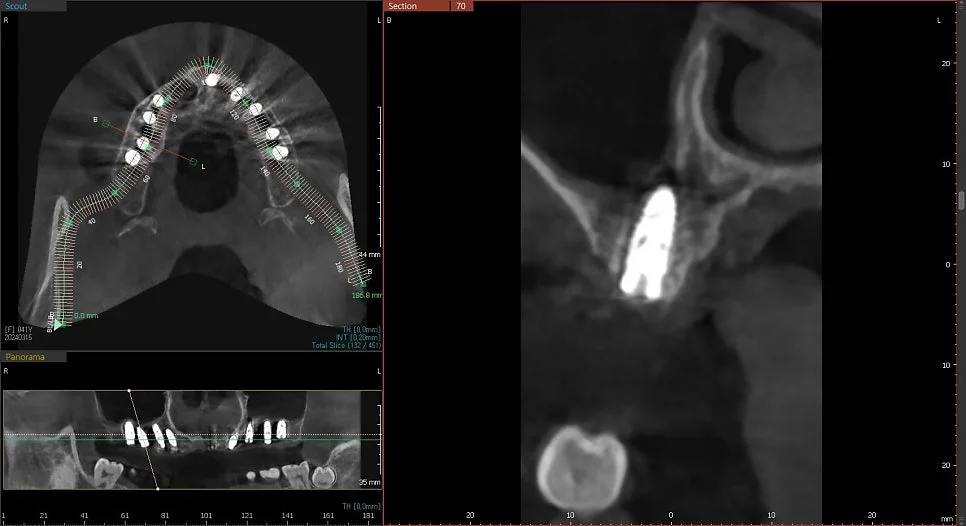

CBCT 단면 – 각 임플란트 개별 검증

CT 상에서 하얀색인 임플란트가 1. 온전히 뼈 안에 잠기게(1~2mm 깊게) 그리고 2. 가급적이면 입천장 쪽으로 식립되었다면 잘 심긴 임플란트입니다. (입술 쪽 뼈는 쉽게 흡수됩니다ㅜ)